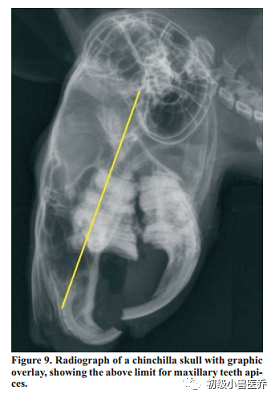

与直接的裸眼的口腔探查相比,口腔内窥镜检查会有更好的质量和口腔内的损伤能更容易观察到。龙猫的口型最适合口腔内窥镜了,因为他们的咬合面是水平的促进了这个检查的进展。这个检查通过看牙龈的大体情况和口腔的粘膜,臼齿临床冠的长度和咬合面的情况,临近空间的大小,和牙齿表面的样子。异常情况像是临床牙冠过长,牙槽和牙峰的改变。臼齿旁舌头和脸颊的偏差(有或没有粘膜破损),和临近牙齿间的宽度增加因此可以见到牙齿间食物的压缩(Capello and Gracis2005)。现在,X光是很常见的基础诊断工具,各种各样的损伤如牙齿重吸收损伤,骨头重吸收和溶解,皮质穿孔,牙根过长,牙齿断裂和缺失都能用X光诊断。但是,需要强调的是正常的X光片不能确定疾病的病理学。很小或特殊的硬组织损伤会被漏诊,直到尸检才被发现(Gracis2008)。放大的X光技术,使用小焦点单位(0.1mm)和一个100mA能量可以作为大小的补偿。一个正常龙猫头颅和牙齿的X光片包括右侧位,背腹位和吻尾位。一个好侧位(LL)可以看到左右侧鼓室,眼眶和下颌关节和腹侧下颌边缘完美重叠(Verstaete2003Gracis2008)。在侧位,本书的作者认为是最有用的一个位置,门齿和切齿都可以评判。上门齿的牙冠不能到达门齿和臼齿间隙长度的2/3,下颚的切齿牙根不能超过第二臼齿(Wiggs and Lobprise1997.门齿咬合表面一般是凿状;,磨损角一般都是上颚的牙齿明显。平坦的咬合面暗示着有牙齿疾病和/或者牙科手术。也有可能是上颌硬腭因为牙齿过度生长而穿孔就会有这个X光影像(Capello and Gracis,2005;Gracis,2008.一般来说,龙猫臼齿咬合面是平整的,差不多是水平的和在侧位片(LL project)上是平行于下颌腹侧边缘的。表面是由光滑的栅栏形成的。为了检查动物是否上颌臼齿过长,要从鼓室的泡门到上门齿背部方向画一条虚拟直线(图9)。如果上颌臼齿牙顶端超过了这条虚线就暗示有这方面的疾病。下颌臼齿尖端很贴近下颌皮质,正常下颌的皮质很薄,很光滑和没有畸形。出现骨头畸形或称之为“突出”强烈暗示下颌臼齿过长。最后,第三种图像(图10)暗示牙冠过长就是上下颌骨间的平行会缺失。背腹部(DV)投影像一般较腹背部(VD)受欢迎是因为背腹部是腹侧摆位,减少了并发呼吸异常的风险。一张好的DVX光应该有一个很完美的对称(在头部左侧和右侧间)。通过这个影像,上下颌骨的边缘,下颌头骨的连接和眼眶的框架都能得到正确评估。异常的像是臼齿过长或生长方向改变都能很容易发现(图11和图12)。另一方面,DV位不适合作为切齿的评估。吻尾位(RC)可以背侧位拍摄(Verhaert2004Capello and Gracis2005.口腔闭合和头部垂直向上与颈部成90度。Bohmer建议开口的RC位,尤其是在评估上臼齿生长过长和颞下颌关节(Bohmer2001a2001b)。RC位提供补充的信息,促进了三个空间去弄明白可能的疾病病理。能明显的观察到牙刺和钉齿,桥接,牙冠和牙尖的生长过长或皮质穿孔。臼齿的角度和咬合面都能测量到。